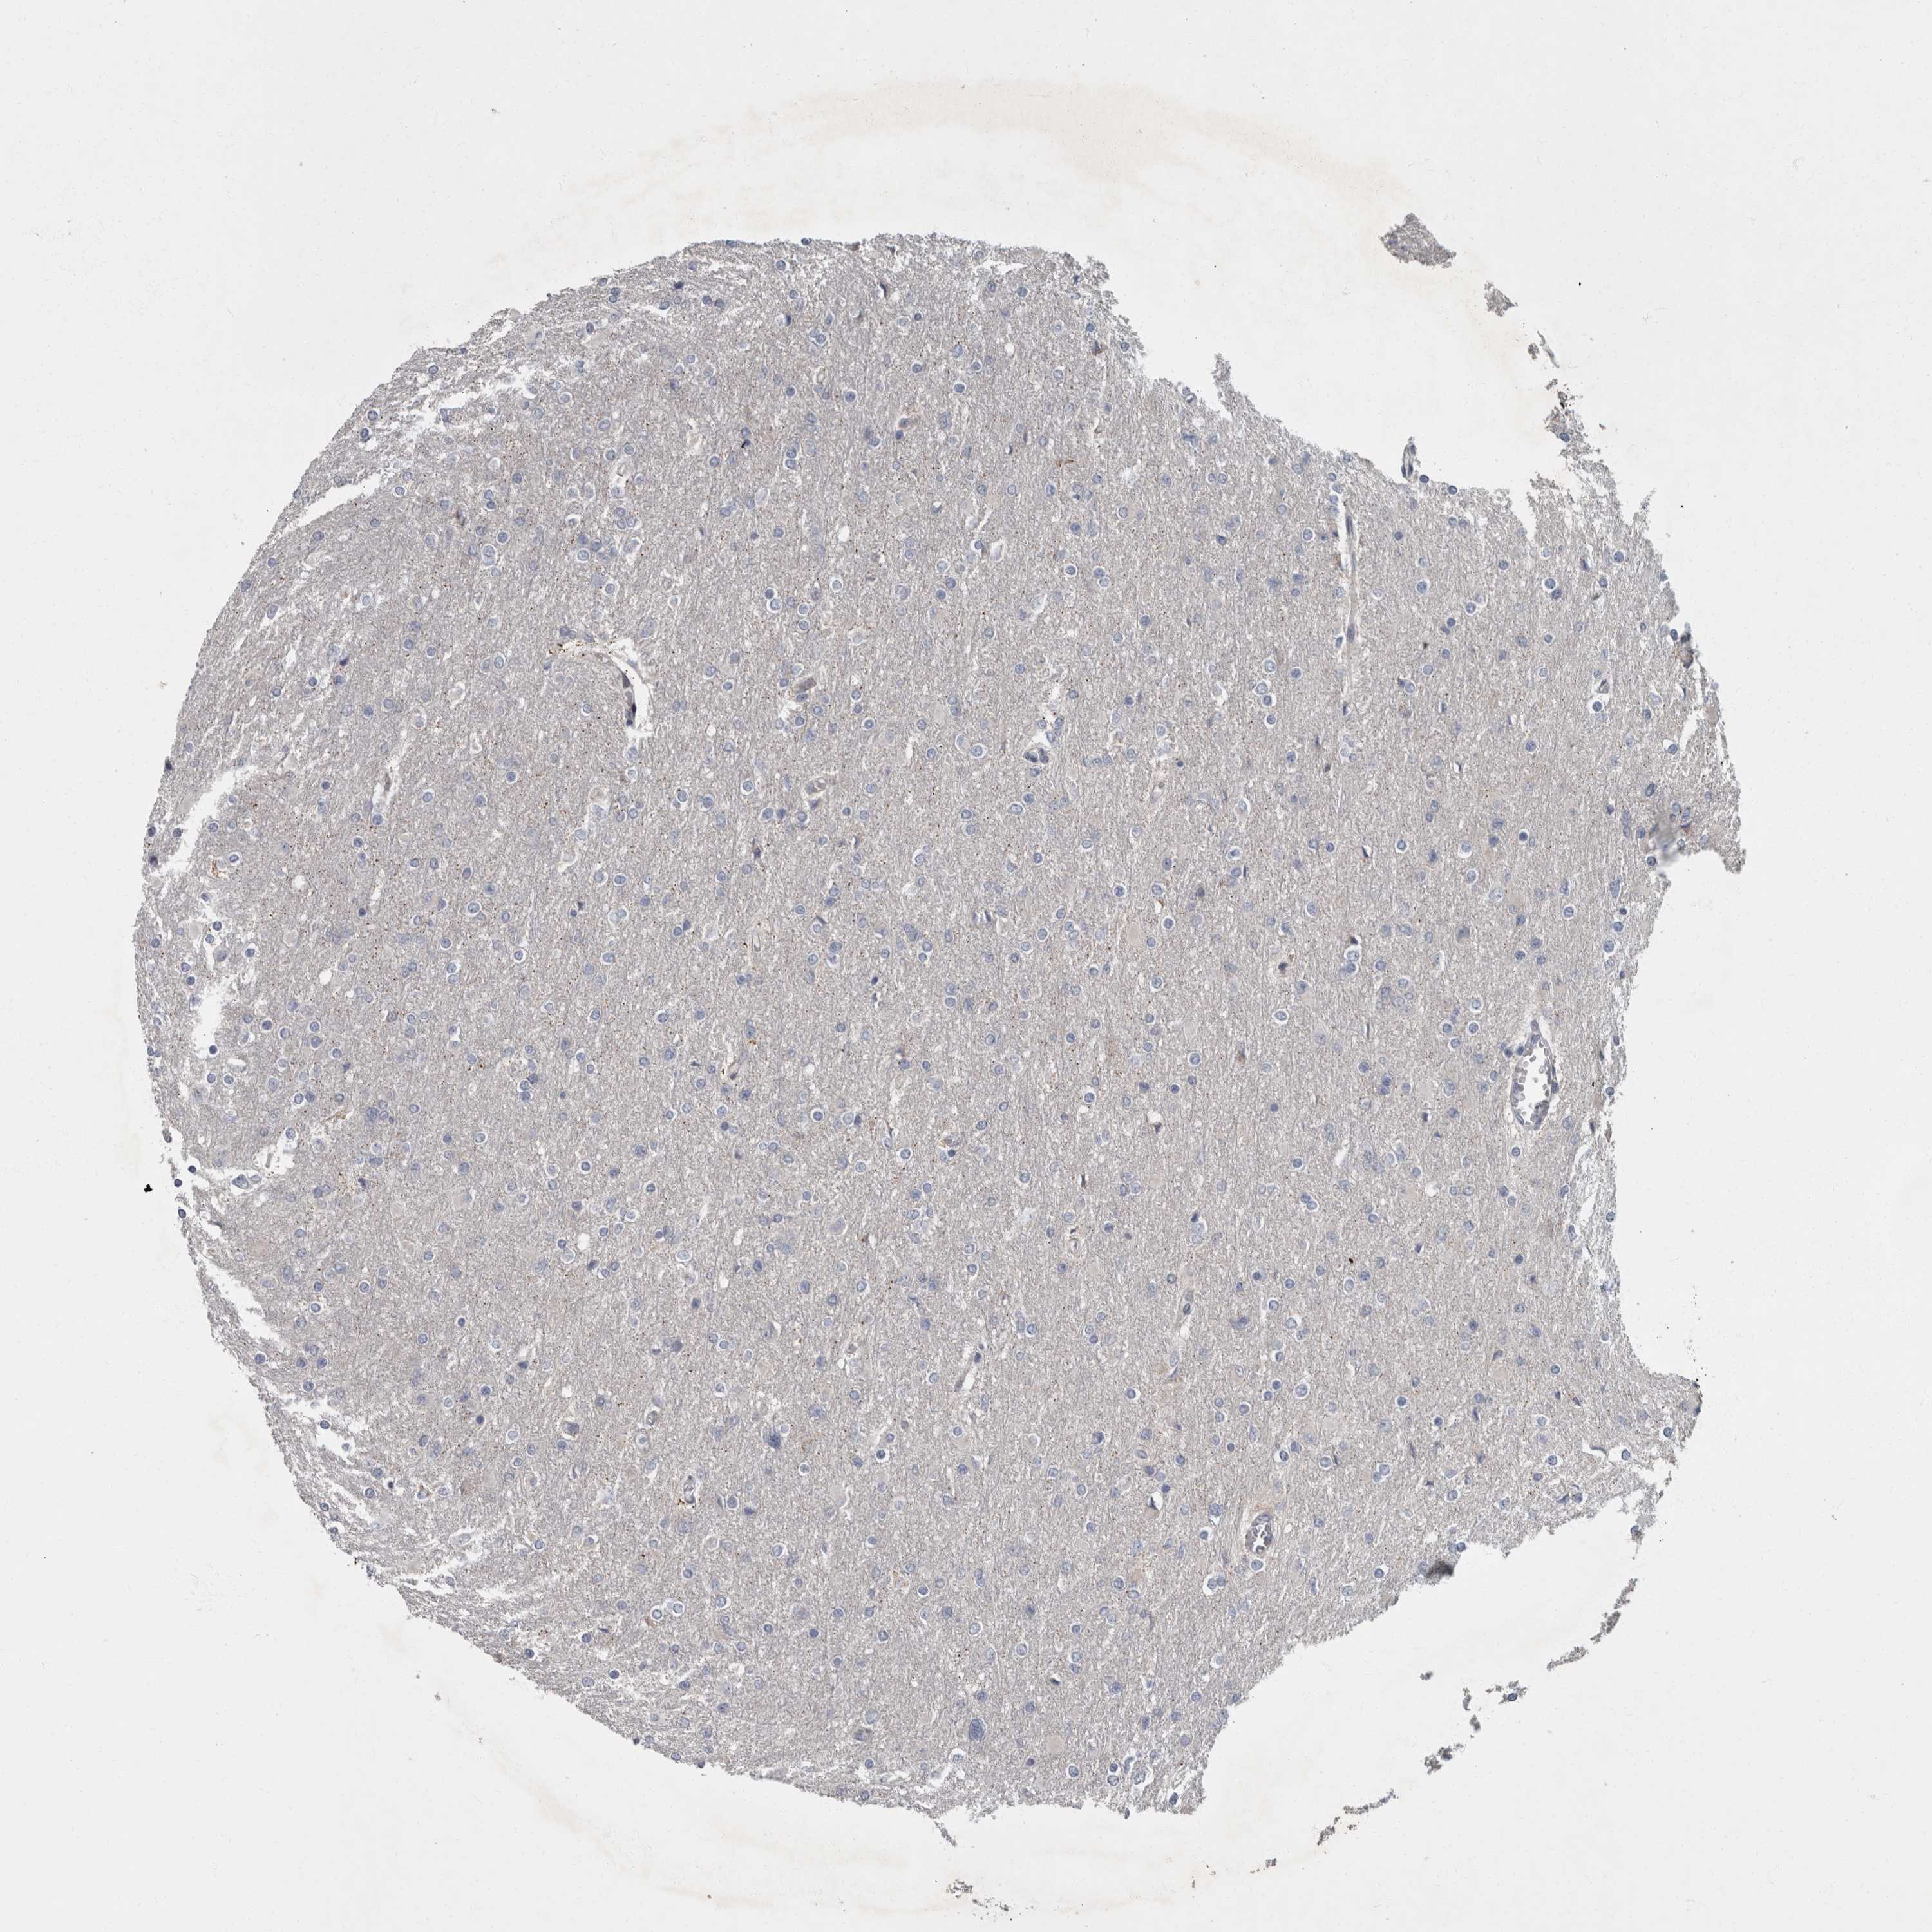

GLIOMA - Protein expressioni

A mouse-over function shows sample information and annotation data. Click on an image to view it in a full screen mode. Samples can be filtered based on level of antibody staining by selecting one or several of the following categories: high, medium, low and not detected. The assay and annotation is described here.

Note that samples used for immunohistochemistry by the Human Protein Atlas do not correspond to samples in the TCGA dataset.

Antibody stainingi

Antibody staining in the annotated cell types in the current human tissue is reported as not detected, low, medium, or high, based on conventional immunohistochemistry profiling in selected tissues. This score is based on the combination of the staining intensity and fraction of stained cells.

Each image is clickable and will lead to virtual microscopy that enables deeper exploration of all samples and also displays staining intensity scores, fraction scores and subcellular localization as well as patient and tissue information for each sample.

Antibody HPA027382

Antibody HPA061836

Staining

High

Medium

Low

Not detected

Intensity

Strong

Moderate

Weak

Negative

Quantity

>75%

75%-25%

<25%

None

Location

Nuclear

Cytoplasmic/membranous

Cytoplasmic/membranous,nuclear

Glioma, malignant, High grade

Glioma, malignant, Low grade